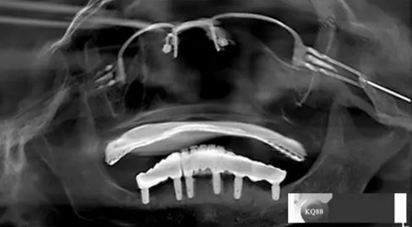

檢查:上頜無(wú)牙頜假牙穩(wěn)定性尚可,下頜3435364243殘根;33殘冠1-2度松動(dòng),其他牙齒缺失;CBCT檢查:下頜牙槽骨前牙區(qū)骨高度足,后牙區(qū)骨高度最低為8mm,骨寬度足。

2)術(shù)前準(zhǔn)備及手術(shù)過(guò)程,測(cè)量血壓及血糖,簽種植知情同意書;嚴(yán)格遵循無(wú)菌操作,局麻下采用微創(chuàng)技術(shù)于323436分別植入osstem4.0X10,4.0X10,4.5X7; 434446分別植入osstem4.0X1O,4.0X10,4.5X7.初期穩(wěn)定性均達(dá)到了35N.CM以上;嚴(yán)密縫合,止血,種植體位點(diǎn)和方向與設(shè)計(jì)一致。

戴牙:試戴,拍片確定邊緣密合后調(diào)整咬合,試戴一周后患者適應(yīng),咬合良好,基臺(tái)加力30N.CM,粘接劑粘固,去除多余粘結(jié)劑,拍片確定有無(wú)粘接劑殘留,并進(jìn)一步微調(diào)咬合